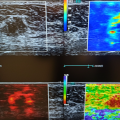

W legnickim szpitalu działa zespół cenionych w Polsce chirurgów naczyniowych, którzy do dyspozycji mają ultranowoczesny sprzęt, m.in aparat ultrasonograficzny klasy premium o wartości 380 tysięcy złotych, a jego zakup sfinansowała Fundacja KGHM Polska Miedź.